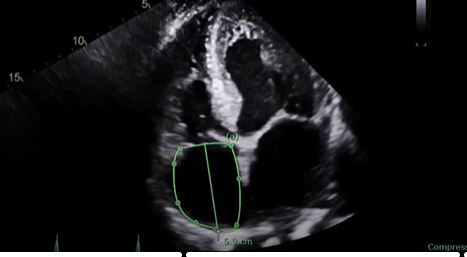

what measurement is this for

RA volume, measure when the chamber is at its largest, just right before the TV open, at end-systole

Trace the chamber excluding the TV annulus

and we also do a length

a normal RA size is going to be less than 19 centimeters squared